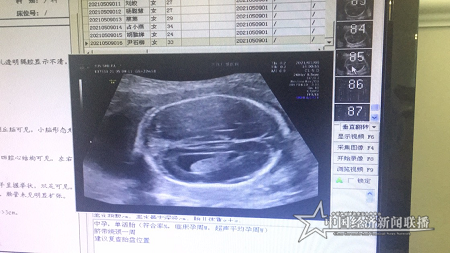

當(dāng)天下午,同樣到仁愛醫(yī)院超聲科做四維彩超檢查的尹女士,也同樣檢查出了胎兒畸形。檢查時(shí)發(fā)現(xiàn),尹女士已孕育21周3天的胎兒,腦部透明隔腔消失、側(cè)腦室呈淚滴狀改變、大腦縱裂池增寬、胼胝體缺失或發(fā)育不良等畸形。

仁愛2.png

胎兒四維彩超影像